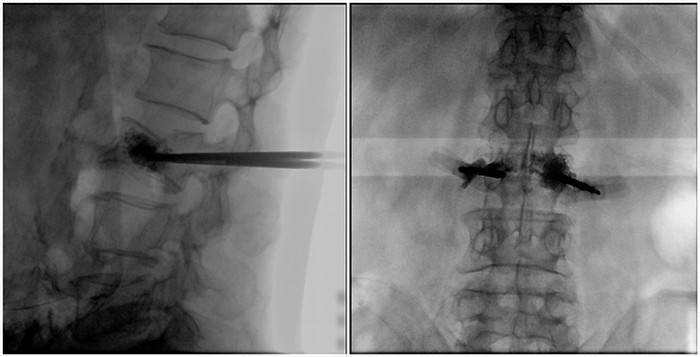

(2)術(shù)中切口5毫米,借助大視野平板C臂機PLX119C的高清圖像,確定進針的方向及進針的深度。經(jīng)椎弓根向椎體置管,建立通道,插入骨擴張器(球囊)。球囊擴張恢復椎體高度,并在椎體內(nèi)形成空腔,確定骨水泥的注入劑量,并注入骨水泥觀察其擴散情況。

大平板C臂機的高清圖像

(3)注射過程需要C臂透視來查看骨水泥的分布情況,預防骨水泥外露進入椎管內(nèi)引起神經(jīng)損傷。椎骨體內(nèi)骨水泥填充完好以后,拔出工作套筒按壓止血,并繼續(xù)俯臥位十分鐘,等待骨水泥硬化,最終手術(shù)圓滿完成。